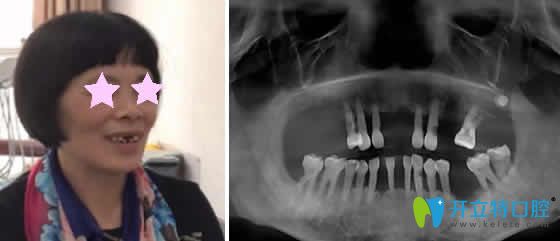

重慶華諾世口腔怎么樣?看李清醫(yī)生微創(chuàng)即刻種植牙案例效果圖:

種植牙前:上邊門(mén)牙兩邊牙齒缺失,吃飯困難。

種植牙后:即刻種植牙當(dāng)天回家能啃蘋(píng)果,而且自然美觀。